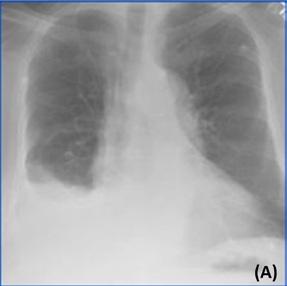

Rapport de radiologie généré par ChatGPT :

Deux radiographies de poumons de face pour contrôle. Celle qui est réalisée récemment (B) montre une amélioration significative de l’état du patient par rapport à la radiographie précédente (A). L’analyse précédente a montré un épanchement pleural, qui est une accumulation de liquide dans l’espace entre les poumons et la paroi thoracique. L’analyse actuelle montre que l’épanchement pleural a disparu. Il n’y a aucune preuve de nouvelles anomalies dans les poumons ou la paroi thoracique. Les poumons semblent bien dilatés et la taille du cœur est normale. Le médiastin, qui est l’espace entre les poumons, se situe également dans les limites normales.

■ Conclusion : L’état du patient s’est amélioré depuis la dernière radiographie thoracique, avec résolution de l’épanchement pleural précédemment constaté. Aucune nouvelle anomalie n’est observée.

■ Avis des radiologistes : Amélioration de l’épanchement pleural.